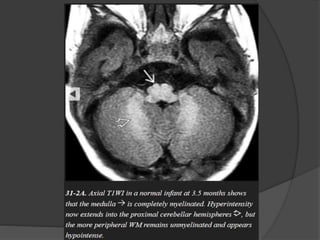

INFRATENTORIAL  Dorsal medulla/ midbrain  Inferior / superior cerebellar peduncles  Middle cerebellar peduncle  Cerebellar white matter T1WI T2WI First appear at Birth Birth Birth Birth 1 mth 3 mth 1 – 3 mth 8 – 18 mth

SUPRATENTORIAL  Internal capsule Posteriorlimb Anterior limb  Thalamus  Pre / postcentral gyri  Corpus callosum Splenium Genu  Centrum semiovale  Optic radiations  Subcortical U fibers T1WI T2WI Birth Birth 3 mth 3 – 6 mth Birth Birth 1 mth 8 – 12 mth 3 – 4 mth 6 mth 6 mth 8 mth Birth – 1 mth 3 mth 3 mth 3 mth 3 – 8 mth 8 – 18 mth

Birth  Dorsal medulla/ mid brain.  Inferior / superior cerebellar peduncles.  Posterior limb of internal capsule.  Ventrolateral thalamus. One month  Deep cerebellar white matter.  Corticospinal tract.  Pre / post central gyri.  Optic nerve / tracts.

Three month  Cerebellarfolia.  Ventral brainstem.  Optic radiation.  Anterior limb of internal capsule.  Occipital subcortical U fibers.  Corpus callosum splenium. Six month  Corpus callosum genu.  Paracentral subcortical U fibers.  Centrum semioval ( Partial ).